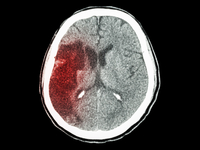

MR CLEAN(血管内治疗急性缺血性卒中)试验的一项新的分析强调快速治疗时间的重要性——每治疗延迟1小时,良好预后机会迅速下降。2015年国际卒中大会上呈现了该治疗时间分析,MR CLEAN的研究者,来自荷兰鹿特丹Erasmus医学中心的Puck Fransen博士总结道:“急性缺血性卒中患者应该进行血管影像检查,并尽快选择合适的治疗策略。”

SWIFT PRIME试验表明,在急性缺血性卒中患者中,对大血管前循环闭塞的患者予以溶栓治疗和Solitaire FR(血流恢复)支架取栓术治疗可减少3个月时卒中致残率并增加患者存活比例和功能独立性。洛杉矶UCLA综合卒中中心的Jeffrey Saver博士在2015年国际卒中大会(ISC)上呈现了这些结果。

对于近端脑动脉闭塞的缺血性卒中患者(存在可挽救性组织)而言,与单独使用阿替普酶相比,采用支架取栓更能改善患者预后。这项研究于2月11日呈现在2015年国际卒中大会上,并同时在线发表于《New England Journal of Medicine》。

ESCAPE试验结果显示,快速血管内治疗可改善功能预后并使近端血管闭塞的缺血性卒中患者的死亡率减半。研究于2015年2月11日呈现在2015年国际卒中大会(ISC)上,并同时在线发表于《New England Journal of Medicine》。